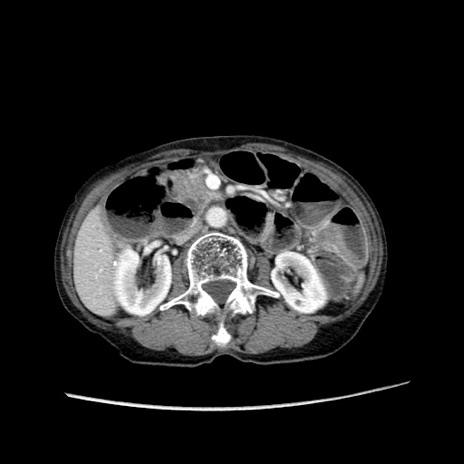

症例25(横断像)

【症例】80歳代女性

【主訴】胸のつかえ感

【現病歴】約9時間前に食後から胸のつかえた感じあり、嘔吐あり、来院。

【既往歴】胃癌(全摘)、胆摘、虫垂炎

【身体所見】心窩部に圧痛あり、反跳痛なし。

【データ】WBC 5700、CRP 0.05